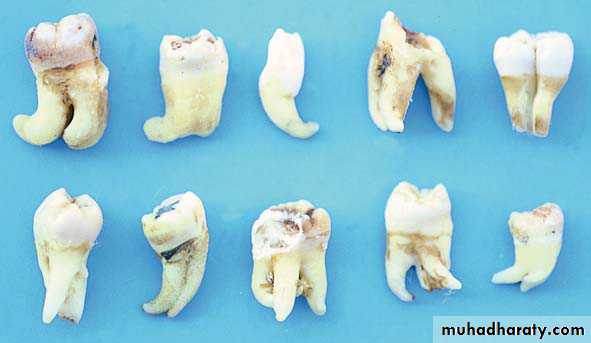

1- Teeth of the maxilla or mandible that present unusualroot morphology

2- Teeth with hypercementosis of root and root tip,

presenting large bulbous roots3- Teeth with dilaceration of root tips

4- Teeth with ankylosed roots or withabnormalities,e.g., dens in dente

2- Extraction of an Intact Tooth with Hypercementosis of the Root Tip

1- a mandibular molar with hypercementosis at the distal root tip.